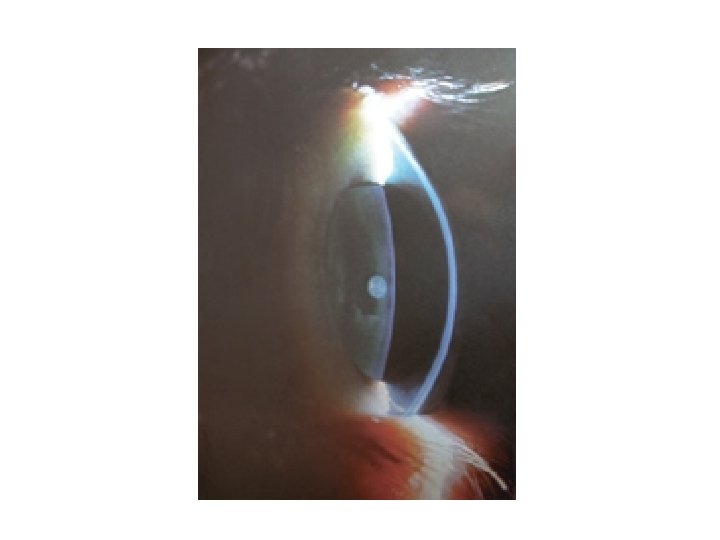

Cataract